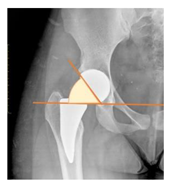

| Acetabular index | The angle described between the line running through the medial edge of the sclerotic acetabular zone and through the lateral sourcil, and its horizontal line | 3–13° | ![]() |